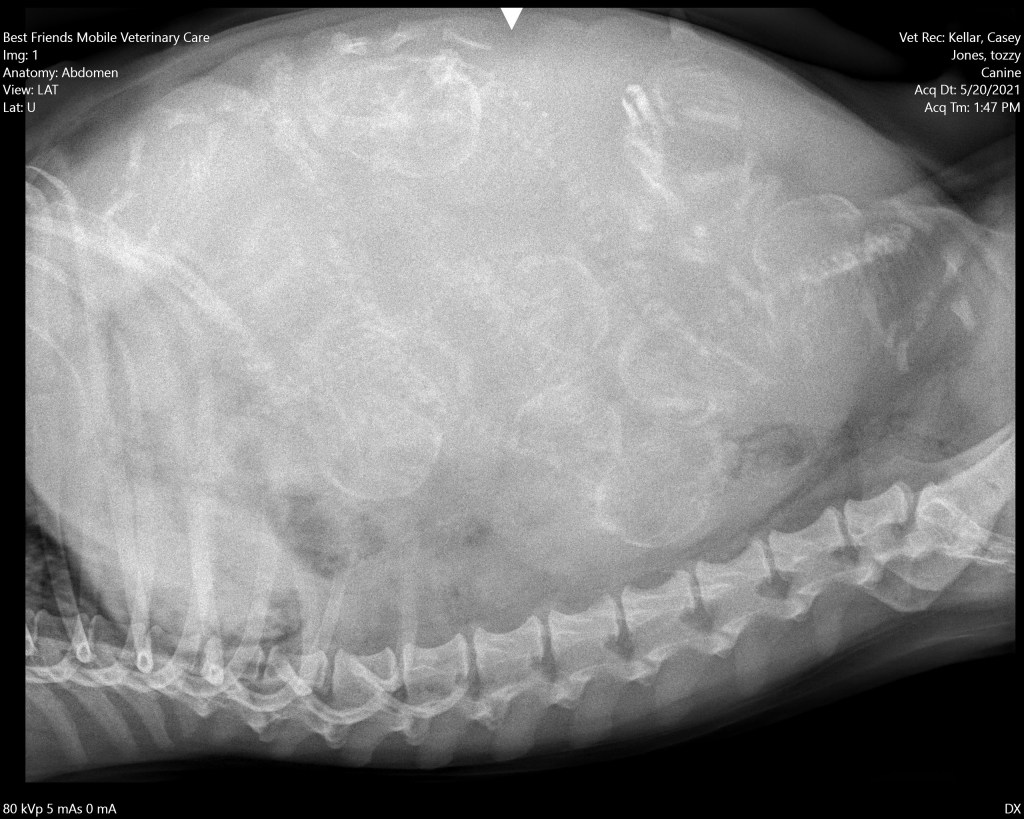

We generally like to get an x-ray one week before they are due. This way we can get a count, though sometimes it isn’t exact because someone can be hidden under something. Also we can be sure no one is too large to fit through the pelvis.

If someone is too big, that is the time to schedule a cesarian section. It is difficult to know the exact date of the females whelping, just like any mammal. You count days and try to figure it. But they still will surprise you. Tahzi was “due” the 26th of May. Instead she went two days after we x-rayed!

But everything went very smooth. She went into labor at 0200 on the 22 of May. She finished birthing 6 healthy puppies.